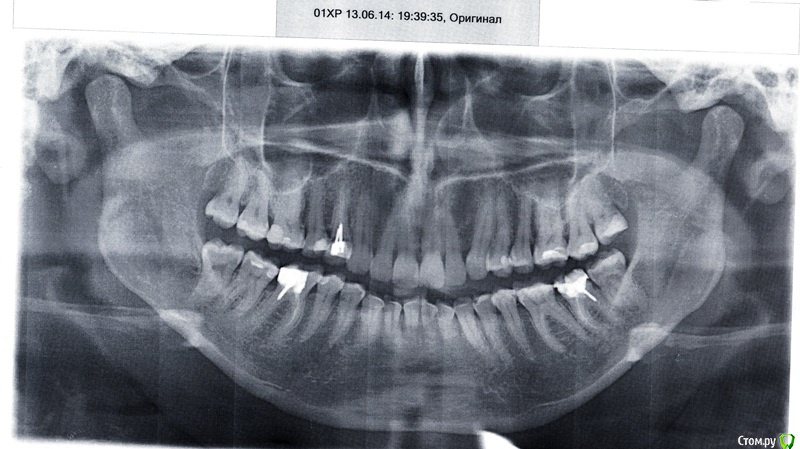

good customer Опубликовано 10 июля, 2016 Автор Поделиться Опубликовано 10 июля, 2016 Добрый вечер, уважаемые Врачи! Нашла панорамный снимок от 2014г. кисты, вроде, не было.... Ссылка на комментарий

Alejandro Опубликовано 12 июля, 2016 Поделиться Опубликовано 12 июля, 2016 Приглядитесь: на этом снимке образование тоже есть. Проверили зуб на витальность? 1 Ссылка на комментарий